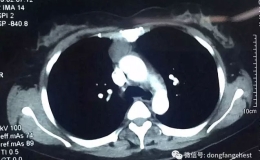

微创小切口下切除纵隔大肿瘤

2017年05月09日,淮南东方总院胸心外科团队,成功利用单孔胸腔镜技术,在仅2cm的小切口下完整切除了困扰患者多年的纵隔肿瘤,术后6小时即可自如活动,术后第1日即拔除胸引管,......